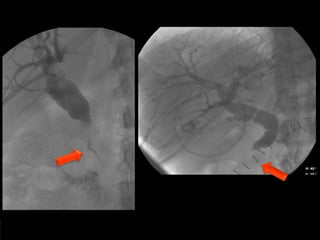

COLEDOCOLITIASIS

RESIDUAL

RESIDUAL CON DILATACIÓN

DE LA VIA BILIAR

• #15 Colangiografia postqx: AP oblicua muestra varias imágenes radiolucidas en via biliar a nivel de colédoco(flechas)